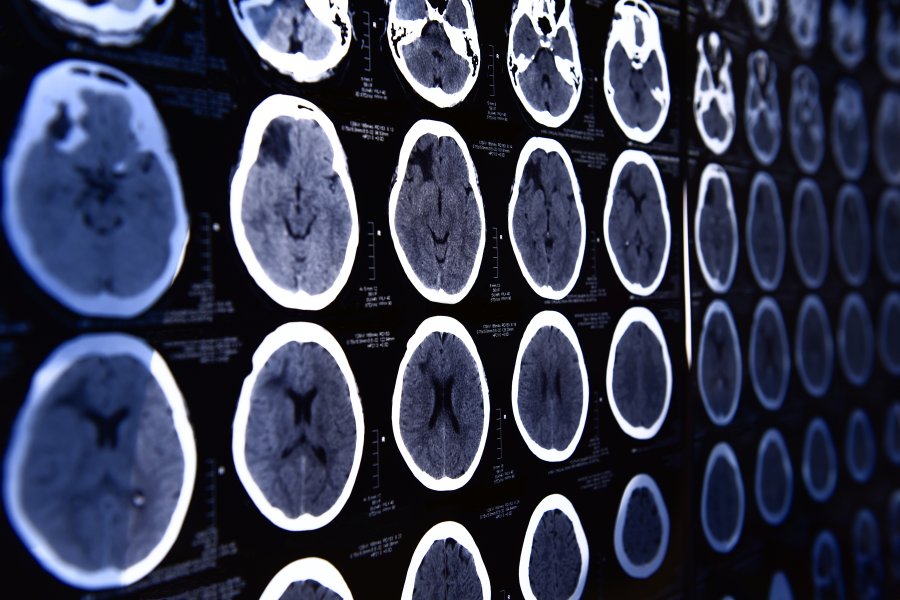

Tomografia komputerowa - na czym polega i kiedy się ją wykonuje?

Tomografia komputerowa, zaliczana do tzw. badań obrazowych, jest jedną z podstawowych metod diagnostycznych wykorzystywanych we współczesnej medycynie. Pozwala na uwidocznienie narządów ludzkiego ciała dzięki wykorzystaniu promieniowania rentgenowskiego. Kiedy lekarz może zalecić wykonanie tomografii komputerowej? Jak należy przygotować się do tego badania?

Tomografia komputerowa, w skrócie TK lub CK (ang. computed tomography) jest obrazową metodą diagnostyki, która wykorzystuje działanie promieni rentgenowskich. Badanie pozwala uzyskać przekroje badanych narządów, a także ich wizualizacje 3D, co bardzo usprawnia proces diagnostyczny. Do wykonania TK wykorzystuje się tomograf, zaś uzyskany za jego pomocą obraz nazywa się tomogramem. Pierwszy raz w celach diagnostycznych tomografię komputerową wykonano na początku lat 70. XX wieku w Stanach Zjednoczonych.

Tomografię komputerową zawsze wykonuje się w oparciu o skierowanie lekarskie. To specjalista określa, czy tomografia komputerowa będzie odpowiedniejsza od innych badań obrazowych. Przeważnie wykonuje się tomografię komputerową głowy i zatok, klatki piersiowej i jamy brzusznej. Najczęstszym wskazaniem do tomografii głowy są nawracające bóle i zawroty głowy, przebyte urazy czaszkowo-mózgowe i w obrębie zatok, niedokrwienia mózgu i udary, a także podejrzenia zmian nowotworowych w obrębie głowy. TK wykonuje się również u osób, które zmagają się z chorobami neurodegeneracyjnymi, jak np. choroba Alzheimera. Skierowanie na to badanie możemy otrzymać od neurologa, onkologa, okulisty, czy laryngologa.